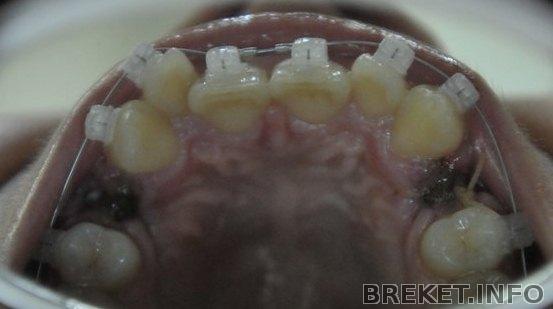

Давно я тут не отмечалась, хотя на сайт заглядываю частенько. А между тем, время идет...уже 2 года, как я в брекетах. Прогресса уже такого заметного, как в начале, нет, все двигается ооочень медленно. О снятии речи пока нет, сейчас двигаем единичку на ВЧ. А сегодня сделала фотки, посмотрела на НЧ, ужас, центр реально сдвинулся в одну сторону на целый зуб(. Сделала коллаж, смотрите.

1д.1г.2г.ВЧ